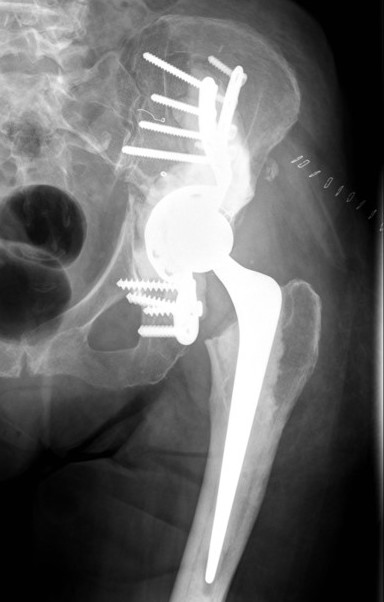

Cup-cage

Cup-cage technique

- 78 patients with Harrington technique versus 37 tantalum acetabular reconstruction

- cup cage in 47 hips with acetabular metastases

- one patient had loosening due to recurrence 8 years post surgery